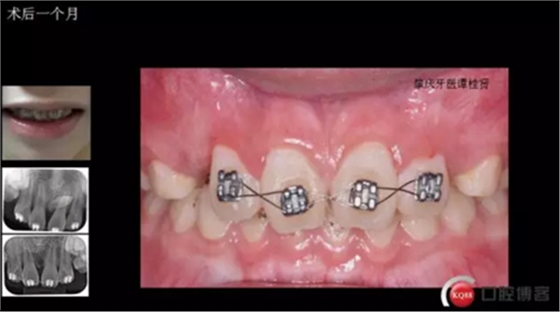

三年半前,家長(zhǎng)領(lǐng)著小孩前來(lái)要求矯正牙齒,男,約八歲,兩中切牙間隙約12MM,有一多生牙,全景片顯示深處還橫著一顆,也許正處叛逆期,小孩非常的調(diào)皮,經(jīng)過(guò)幾次的各種哄和商談,也可能為了好看,終于勉強(qiáng)同意先拔掉露出的多生牙,前牙片斷弓關(guān)閉間隙

拔掉一顆后大概大半年時(shí)間很快就把間隙關(guān)閉了,但是由于還有一顆橫在兩中切牙間,牙縫始終得不到完全關(guān)閉,此時(shí)只能拔掉深部埋伏阻生的牙才能進(jìn)一步矯正治療,但小孩一聽(tīng)又要做一次手術(shù)有不同意了,這樣又拖了兩年多,長(zhǎng)大了一些自然懂事了些。